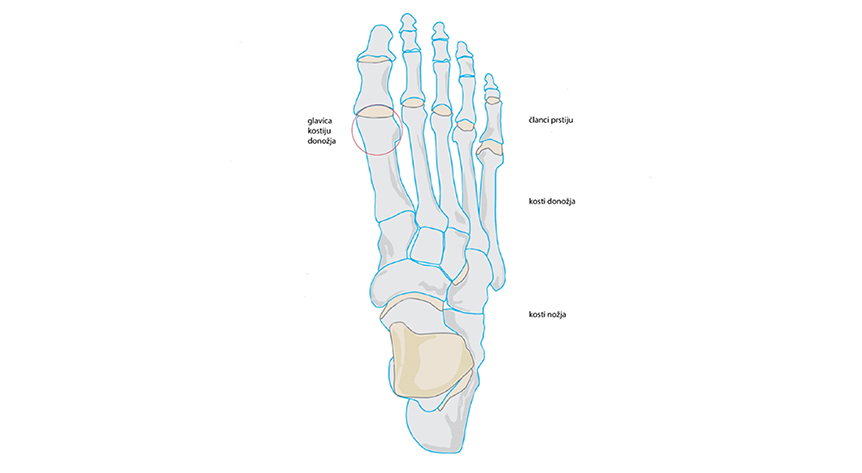

Stopalo ima specifičan izgled, a formiraju ga 26 kostiju međusobno povezanih zglobovima, manje ili više pokretnih. Osnovni izgled stopala sličan je lučnom mostu, kojeg formiraju nekoliko uzdužnih i poprečnih svodova. Same svodove podržavaju mali mišići stopala i potkoljenice. Dokle god je snaga mišića stopala u ravnoteži sa silama opterećenja koje djeluju na stopalo, ono ima svoj optimalni anatomski izgled uz dostatnu funkciju.

Kod ovog tipa zahvata gdje već postoje degenerativne promjene na bazalnom zglobu palca izvodi se uz plastiku zglobne kapsule. Time se korigira položaj palca. Kod ovog tipa operativnog zahvata nema nikakve imobilizacije. Dopušteno je opterećenje stražnjeg dijela stopala, odnosno korištenje posebnih ortopedskih cipela namijenjenih samo za postoperativni tijek. Kod svih vrsta operativnih zahvata, bilo mlađih ili starijih osoba, uvijek se obavezno odstrani koštana izraslina s vanjske strane glavice I. metatarzalne kosti. Postoji pet metatarzalnih kostiju koje se broje od palca prema malom prstu.

Vrlo česta pojava kod poprečno spuštenih svodova stopala je pojava boli u prednjem dijelu stopala- tzv. metatarzalgija uz koju se u kasnijoj fazi mogu pojaviti i bolni natisci na tabanu ispod glavica kostiju donožja.

Ako se i nakon fizikalne terapije ne ostvare određeni rezultati, već se bolni natisci i dalje povećavaju te stvaraju sve veće subjektivne tegobe. Tada se stopalo mora operirati, ali jednostavnim zahvatom. Bit zahvata je rasterećenje u području glavica kostiju donožja. Izvodi se kosa osteotomija iza glavice kosti donožja tako da se glavica minimalno pomiče prema gore i u smjeru gležnja. Drugi dan osoba staje na noge skoro s maksimalnim opterećenjem, a bol koja je bila ispod glavice više ne postoji. Jedino je prisutna bol s gornje strane stopala gdje je učinjen operacijski rez.